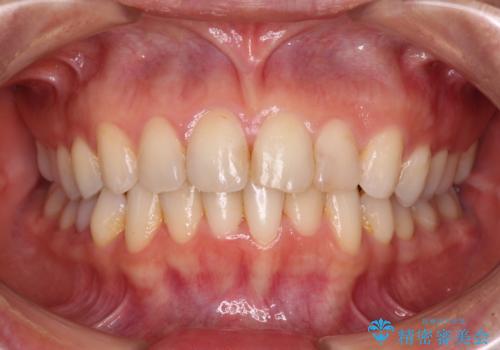

前歯の叢生をいつの間にか改善 インビザラインによる矯正治療

下顎善の叢生をもう少し改善したかったのですが、患者様は十分に整ったとのことで治療を終えることになりました。